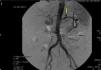

Following review of all the findings, it was decided to perform axial computed tomography (CT) with contrast. This revealed the presence of a hyperdense nodule in the posterior region of the gastric fundus compatible with pseudoaneurysm of the left gastric artery, with an underlying haematoma (Fig. 1). Percutaneous transcatheter embolization of the pseudoaneurysm was performed with the use of coils, with satisfactory control of bleeding as per angiography (Fig. 2).